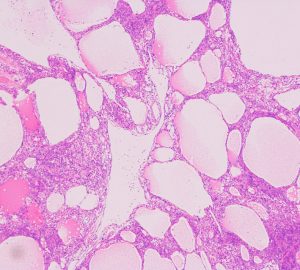

xanthomatous change 黄色腫様の髄膜腫

小脳橋角部に発生した髄膜腫ですが,手術中に見た目に真っ黄色で柔らかく,繊維成分のない壊れやすい脂肪組織を摘出しているようでした。

xanthomaとも表現できるほどfoamy macrophagesの浸潤の目立つ組織です。

MIB-1染色率は8-10%と高く,臨床的にはグレード2に近い性格を示すものです。